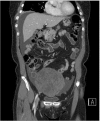

Meigs' syndrome is a benign ovarian tumor associated with ascites and pleural effusion. Elevated cancer antigen 125 (CA-125) in Meigs' syndrome is an unusual clinical condition reported in few cases. We report here on a 61-year-old woman who presented with dyspnea; in imaging assessment, a heterogeneous pelvic mass measuring 12 × 11 cm with ascitic fluid was reported. Pleural effusion was detected on Chest X-ray. Aspiration of pleural fluid showed no evidence of malignancy. CA-125 level was 347 IU/mL. The patient underwent laparotomy during which a mass measuring 12 × 11 cm was detected in her left adnexa. Histology showed ovarian thecoma. The mass was resected, and, after that, the symptoms disappeared and CA-125 level reached 19 IU/mL. The patient had experienced no problem after 12 months of follow up. Although postmenopausal women with ovarian tumor, ascites, pleural effusion, and elevation of CA-125 levels probably have malignant ovarian tumors, Meigs' syndrome must be considered in the differential diagnosis.